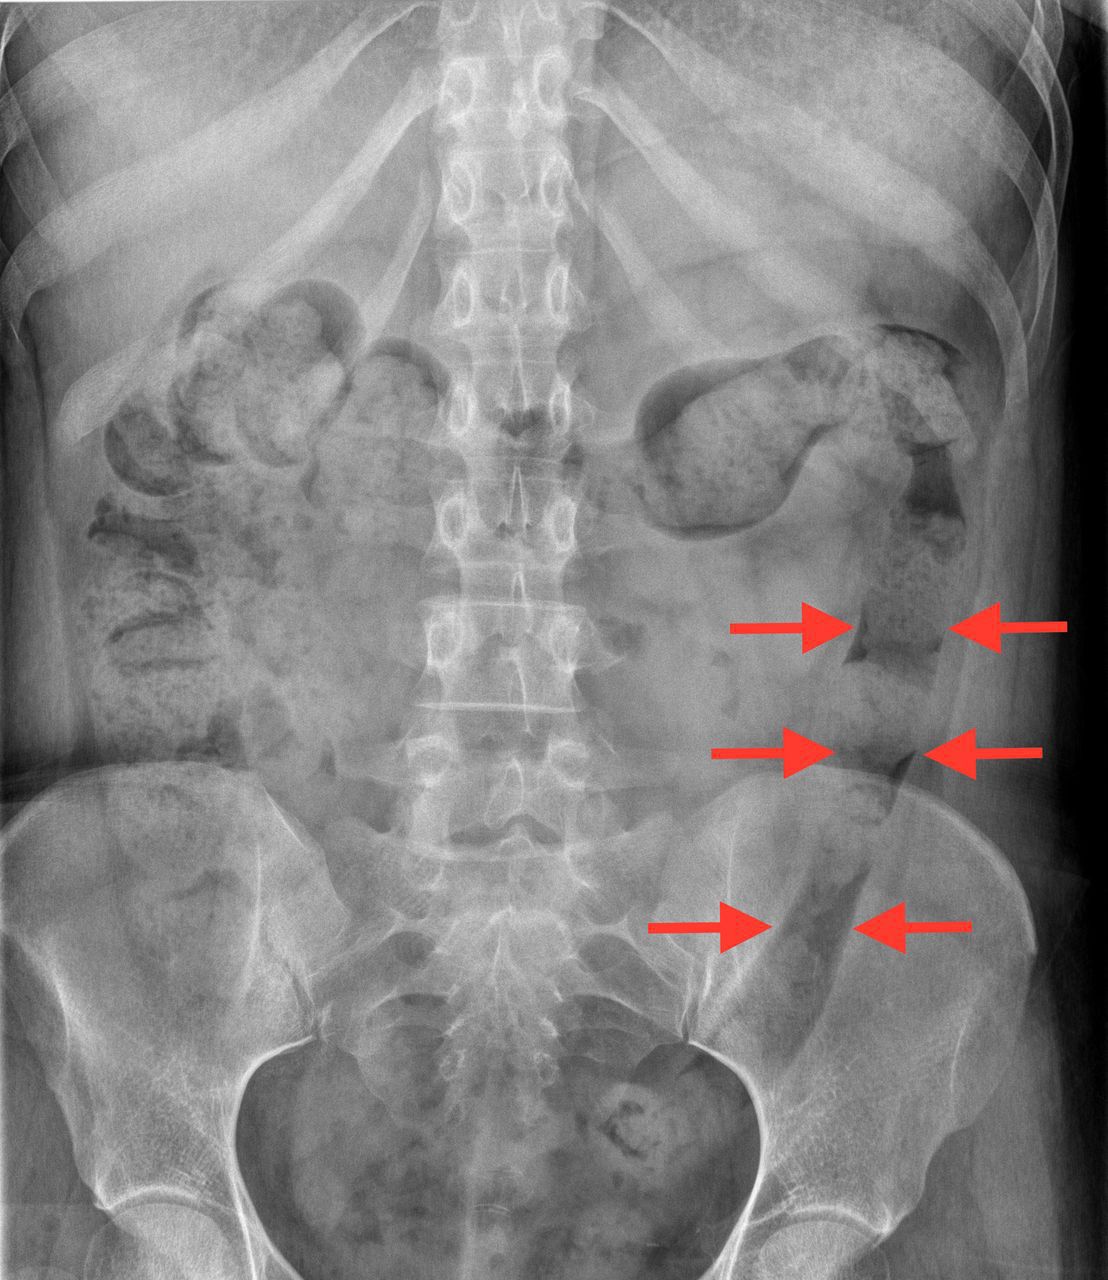

Lead pipe appearance on X-ray from loss of haustration in a patient with Ulcerative Colitis

Lead pipe appearance is characteristic of u.c that begins in rectum.